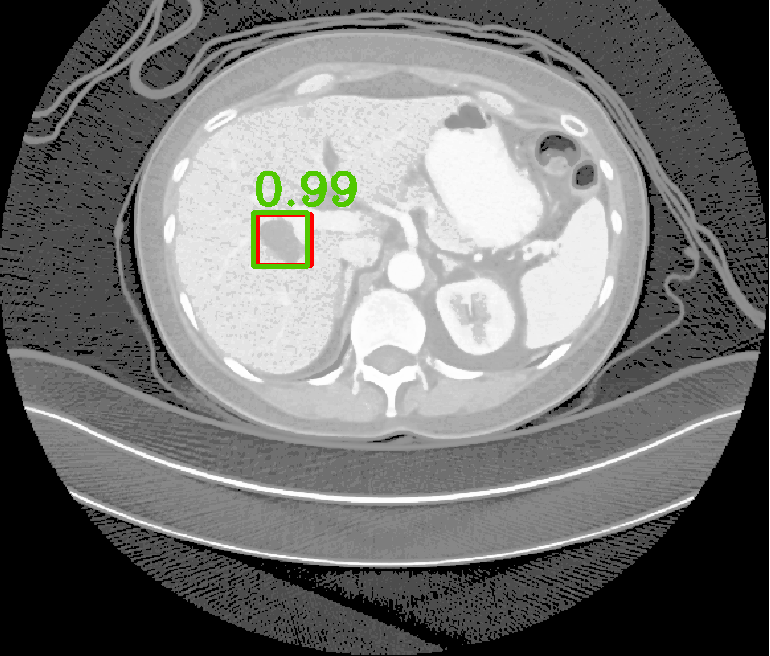

| (a) Ground Truth | (b) Faster R-CNN | (c) FPN | (d) Proposed |

In real-world scenarios, body lesions usually have arbitrary size. For instance, in the DeepLesion [14] dataset, the lesion size ranges from 0.21 mm to 342.5 mm. Since most of the established CNNs are not robust to handle such spatial scale variations, they have unpredictable behavior in the varying cases. As shown in Fig. 1, both Faster R-CNN and FPN fail to detect tiny lesions in the first row, while they produce small false positive lesions around the actual large lesion locations in the second and third rows.

In this paper, we propose a fine-grained lesion detection approach with a novel multi-scale attention mechanism. We use 2D FPN as the backbone to construct the feature pyramid in a relatively coarse scale. Within each level of the feature pyramid, we propose to use a Multi-Scale Booster (MSB) to facilitate lesion detection across fine-grained scales. Given the feature maps from one pyramid level, MSB first performs Hierarchically Dilated Convolution (HDC) that consists of several dilated convolution operations with different dilation rates [15]. The feature responses from HDC contain fine-grained information that is complementary to the original feature pyramid, which is achieved by extensive feature extraction in 2D space. The over-sampled feature responses are then concatenated and further exploited by channel-wise and spatial-wise attention. The channel attention module in MSB explores different lesion responses from the subchannels of the concatenated feature maps. The spatial attention module in MSB locates lesion response within each attentive channel. The channel-wise and spatial-wise attention modules enable the network to focus on particular lesion responses offered by the fine-grained features, while annealing the irrelevant and interference information. Thorough experiments demonstrate that MSB improves the deep pyramid prediction results and performs favorably against state-of-the-art approaches on the DeepLesion benchmarks.